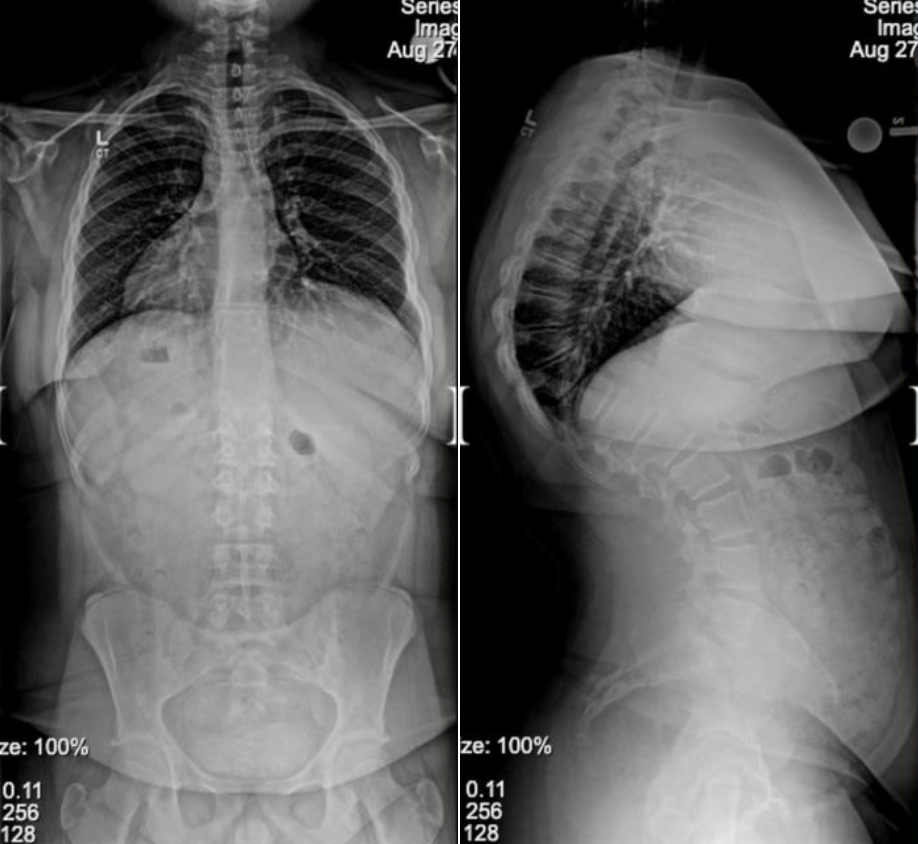

Below are before and after photos of two of our patients who underwent a posterior spinal fusion, one for scoliosis and one for kyphosis.

Scoliosis